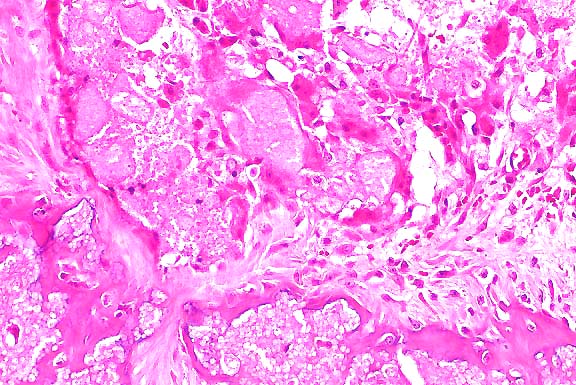

- Iliac, subvertebral mass: There is a dense fibrous capsule

of some section borders which contains individualized and flattened

bone multifocally. There is abundant, moderately cellular stroma

with flattened to plump spindle cells and abundant mature collagen.

Multifocally, there is a lightly basophilic matrix that stains

with alcian blue for mucopolysaccharide. Scattered foci of more

dense homogenous eosinophilic stroma with embedded nuclei are

noted. There are discrete islands of multinucleate giant cells

that have approximately 6 to up to 30 nuclei, and abundant eosinophilic

cytoplasm. These cells surround and are occasionally found within

small non-muscular vessels. The cytoplasm occasionally contains

iron positive hemosiderin material, or has small cleft-like vacuoles.

These latter cells often have light blue staining of the cytoplasm

with alcian blue. The vessels are variably congested, with some

small foci of hemorrhage and a few hemosiderophages. Trichrome

staining reveals abundant collagen throughout, positive staining

in more homogenous stromal areas, and occasionally centrally

around multinucleate giant cells.

- Case 20-3. Tumor. Normal bone is replaced by streams

& bundles of spindle cells and multifocal clusters of multinucleate

giant cells.